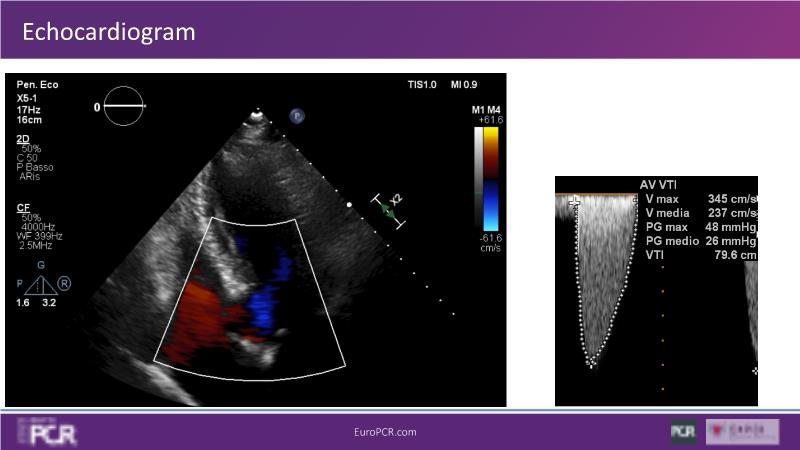

Discover the key factors to consider in selecting the optimal valve and implant technique for transcatheter aortic valve implantation (TAVI) to achieve optimal procedural outcomes. Gain insights into the impact of device choice and implantation technique on coronary access following TAVI and learn valuable strategies for tailoring your TAVI technique to complex scenarios, including bicuspid aortic valves, large and calcified anatomies, and ensuring coronary access.

- To learn how to tailor your TAVI technique to complex situations: bicuspid aortic valves, large, calcified anatomies and coronary access